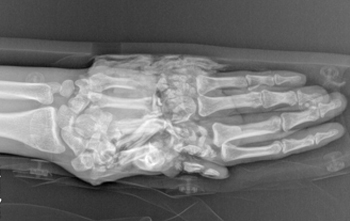

科室在肢体严重撕脱创伤、复杂断指(肢)再植、各类型游离足趾移植拇手指再造或组合再造、游离皮瓣修复四肢缺损创面等方面取得显著成绩,受到了省内外专家和广大患者高度评价。近年来,科室不断拓宽诊治范围,深耕手病专科,如腱鞘炎、周围神经损伤、肌腱修复等,在腕关节镜微创治疗方面取得了长足的进步,形成了自己的治疗特色。

◎ 断指(肢)再植 ◎ 游离足趾移植拇手指再造或组合再造

◎ 手部疾病:腱鞘炎、周围神经损伤、肌腱修复等

擅长:四肢显微修复及功能重建;特殊类型断指(肢)再植,小儿断指再植;拇手指全型再造;小儿手足先天性畸形矫形、烧伤瘢痕整形;四肢骨缺损、手部各种肿瘤、周围神经损伤的诊治;腱鞘炎、周围神经损伤、肌腱修复等;腕关节镜的微创治疗